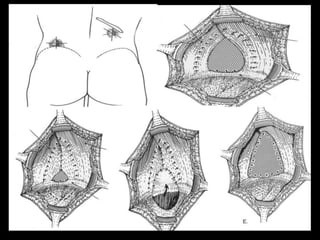

Técnica quirúrgica

• Combinación de técnica de Rives + Bendavid con

colocación de malla de polipropileno

• La malla se coloca preperitoneal y retropúbico y

se fija con prolene a las siguientes estructuras:

• Ligamento arcuato

• Cara posterior del pubis

• Ambos ligamentos de Cooper

• Los músculos rectos lateralmente y sus aponeurosis con

puntos en U sobre ellas, y sin tensión en la línea de sutura

• Uso de drenaje subcutáneo